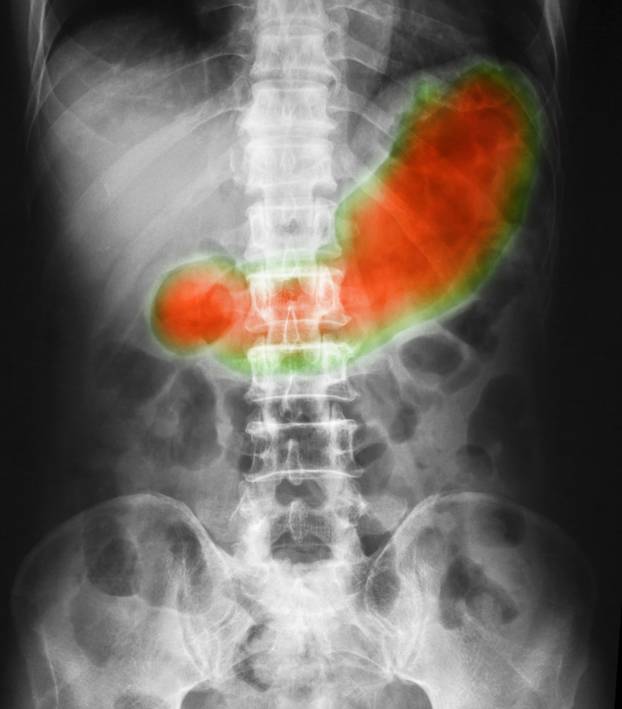

SLIKOVNE PRETRAGE Rendgenske snimke gornjeg dijela probavnog sustava koriste se u dijagnostici. Omogućuju uočavanje čireva i oštećenja želuca. Ove pretrage pomažu u procjeni težine bolesti. Često se koriste prije endoskopije.